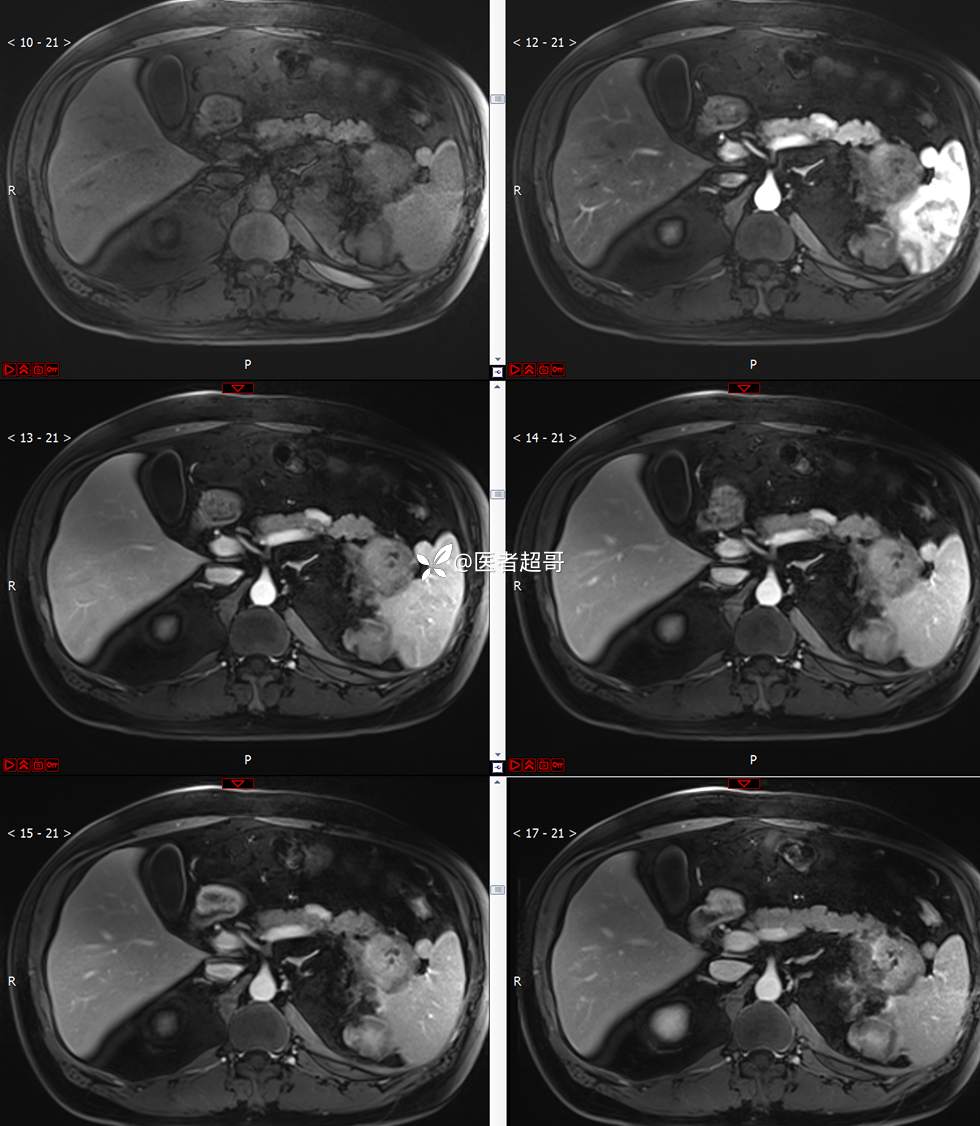

主 诉:查体发现左肾肿物9天。

现病史:患者9天前于附属医院行常规腹部CT检查时,发现左肾占位性病变并肾周脂间隙软组织增多,自述无明显腰腹部不适,无尿频、尿急、尿痛及肉眼血尿,未予特殊治疗,患者近期无头晕头迷,胸闷气急,腹胀腹泻及其他部位明显不适,遂至我院就诊,门诊以“肾肿物”收入院,患者自发病以来,精神可,睡眠饮食可,大便正常,体重无明显减轻。